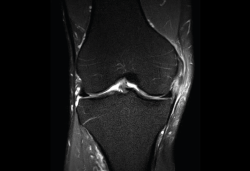

4.3. Osteocondritis

En la osteocondritis se aprecia una lesión subcondral caracterizada por resorción ósea, colapso y la formación de un secuestro.

El estudio por RM es una herramienta valiosa para diagnosticar e identificar las lesiones del cartílago. Conocer el aspecto del cartílago y saber cuánto y cuándo se lesiona, basándose en las clasificaciones actuales, permiten al radiólogo proporcionar la máxima información al clínico(20).

Figura 53. Corte de secuencia sagital (A) y axial (B) T2 Fat-Sat de RM de rodilla: lesiones osteocondrales en el fémur y la rótula.

Numerosos estudios demuestran la utilidad de la RM para definir la estabilidad o inestabilidad de la lesión en la osteocondritis, destacando su carácter no invasivo y la capacidad de valorar la progresión y la respuesta al tratamiento(21)(Figuras 53 y 54).

Figura 54. Corte de secuencia T1 y T2 Fat-Sat coronal de resonancia magnética: gran osteocondritis en el cóndilo femoral interno con edema en la medular adyacente.